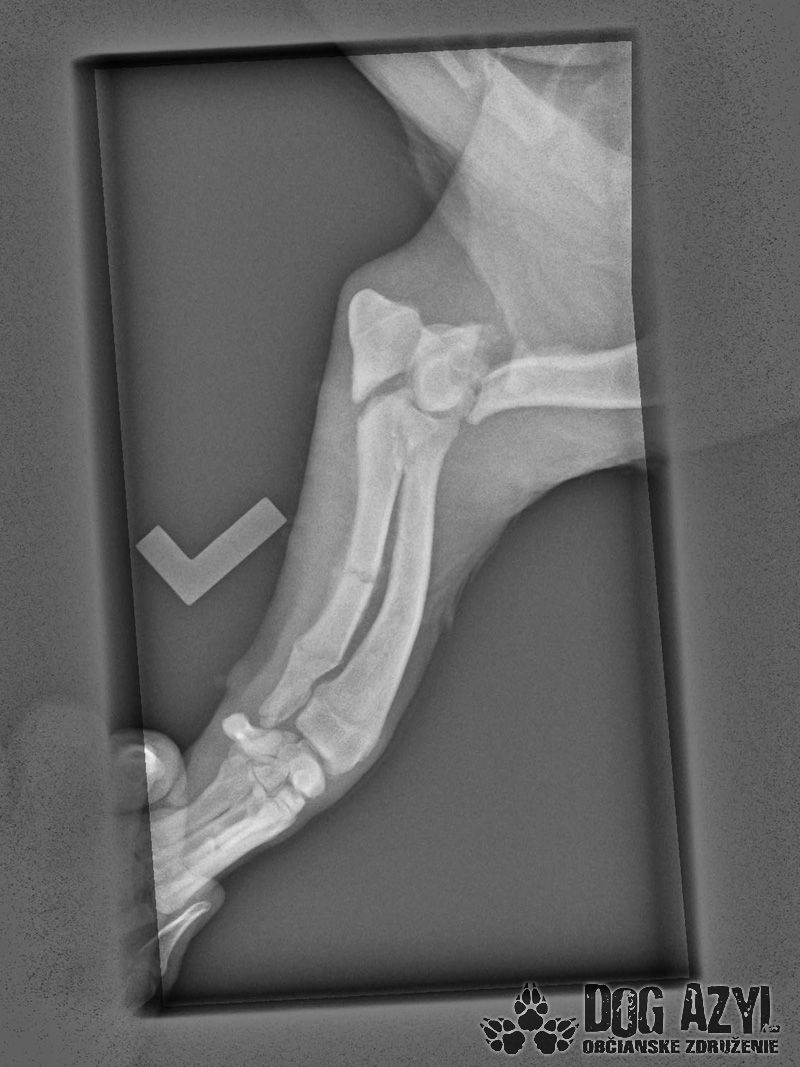

Skip bol nájdený 7. mája 2015 v jarku medzi Veľkým Mederom a Dolným Štálom, mal šťastie, pretože práve na tejto ceste je jarok veľmi hlboký, Skip sa ale vyplazil na cestu a hľadal pomoc. Ihneď sme ho naložili do auta a utekali sme s ním k nášmu pánovi doktorovi, keďže nám bolo jasné, že to nebude iba udretie, čo musíme riešiť, Skip nám pod rukami pukal pri každom dotyku a odovzdane nám pozeral do očí, vedel, že už bude dobre, že mu pomôžeme. Išli sme najprv na RTG, celú dobu sa nechal polohovať a pozeral nám pri tom do očí, zmierený s osudom, zrejme si povedal, že viac, ako to bolí, to už bolieť nebude. Z prvých snímkov je viditeľné, že má zlomený lakeť ľavej prednej nohy a aj kosti tam má polámané, takisto má zlomenú ľavú zadnú nohu, panva zatiaľ zlomeninu neukázala, ale uvidí sa pri podrobnejšom vyšetrení v pondelok, kedy pôjde na operáciu. Faktom však je, že to nebolo úplne čerstvé zranenie, takže v tej priekope ležal už niekoľko dní, ten, čo ho zrazil, ho tam bezcitne nechal napospas osudu a Skip v bolestiach čakal na smrť.